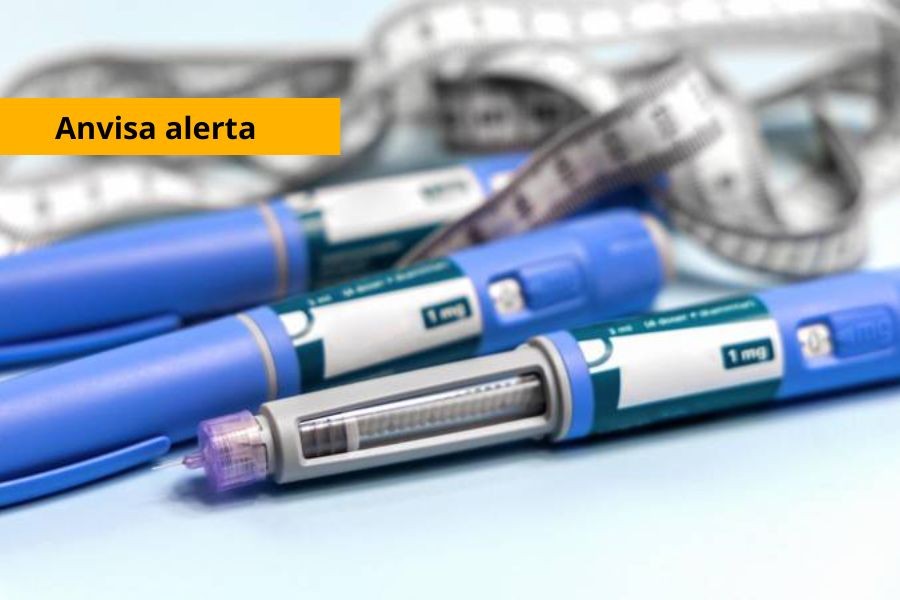

Anvisa informa sobre proibição de ingresso de canetas emagrecedoras no Brasil

Medicamentos sem registro no país só podem ser importados de forma excepcional e para uso exclusivamente pessoal, mediante prescrição médica e cumprimento de requisitos adicionais.